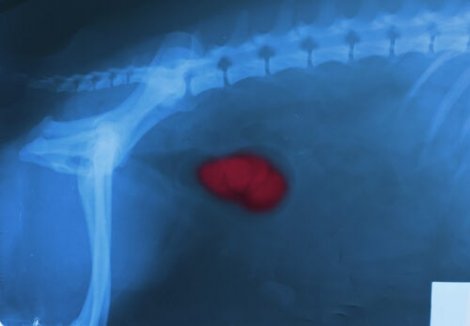

Neoplasi

Neoplasi, elakartade eller godartade, är onormala utväxter av vävnad i specifika delar av kroppen. Det kan röra sig om hyperplasi i prostatan, hemangiom eller hemangiomsarkom.